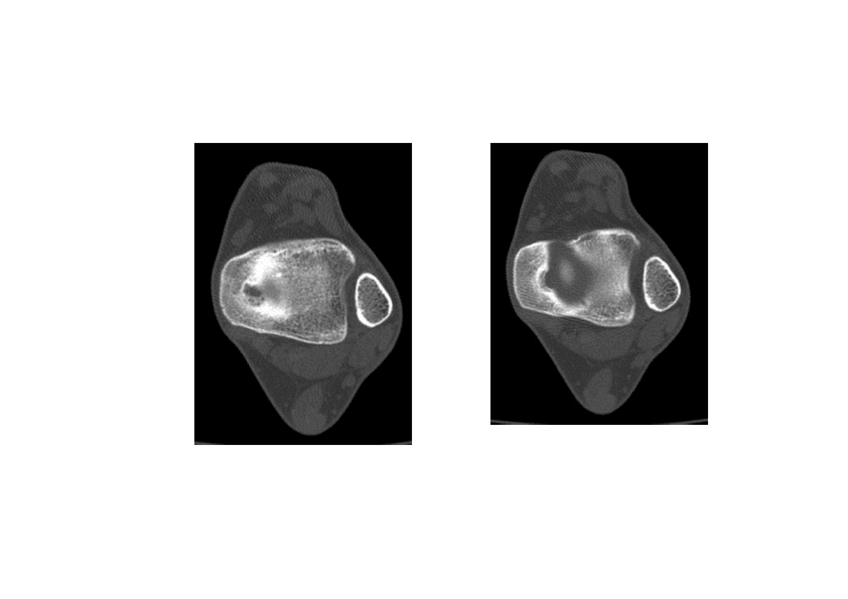

rodilla

He publicado nuevos apuntes de Técnicas de Tomografía Computarizada y Ecografía: rodilla

genoll-tc-Modo-de-compatibilidad.pdf